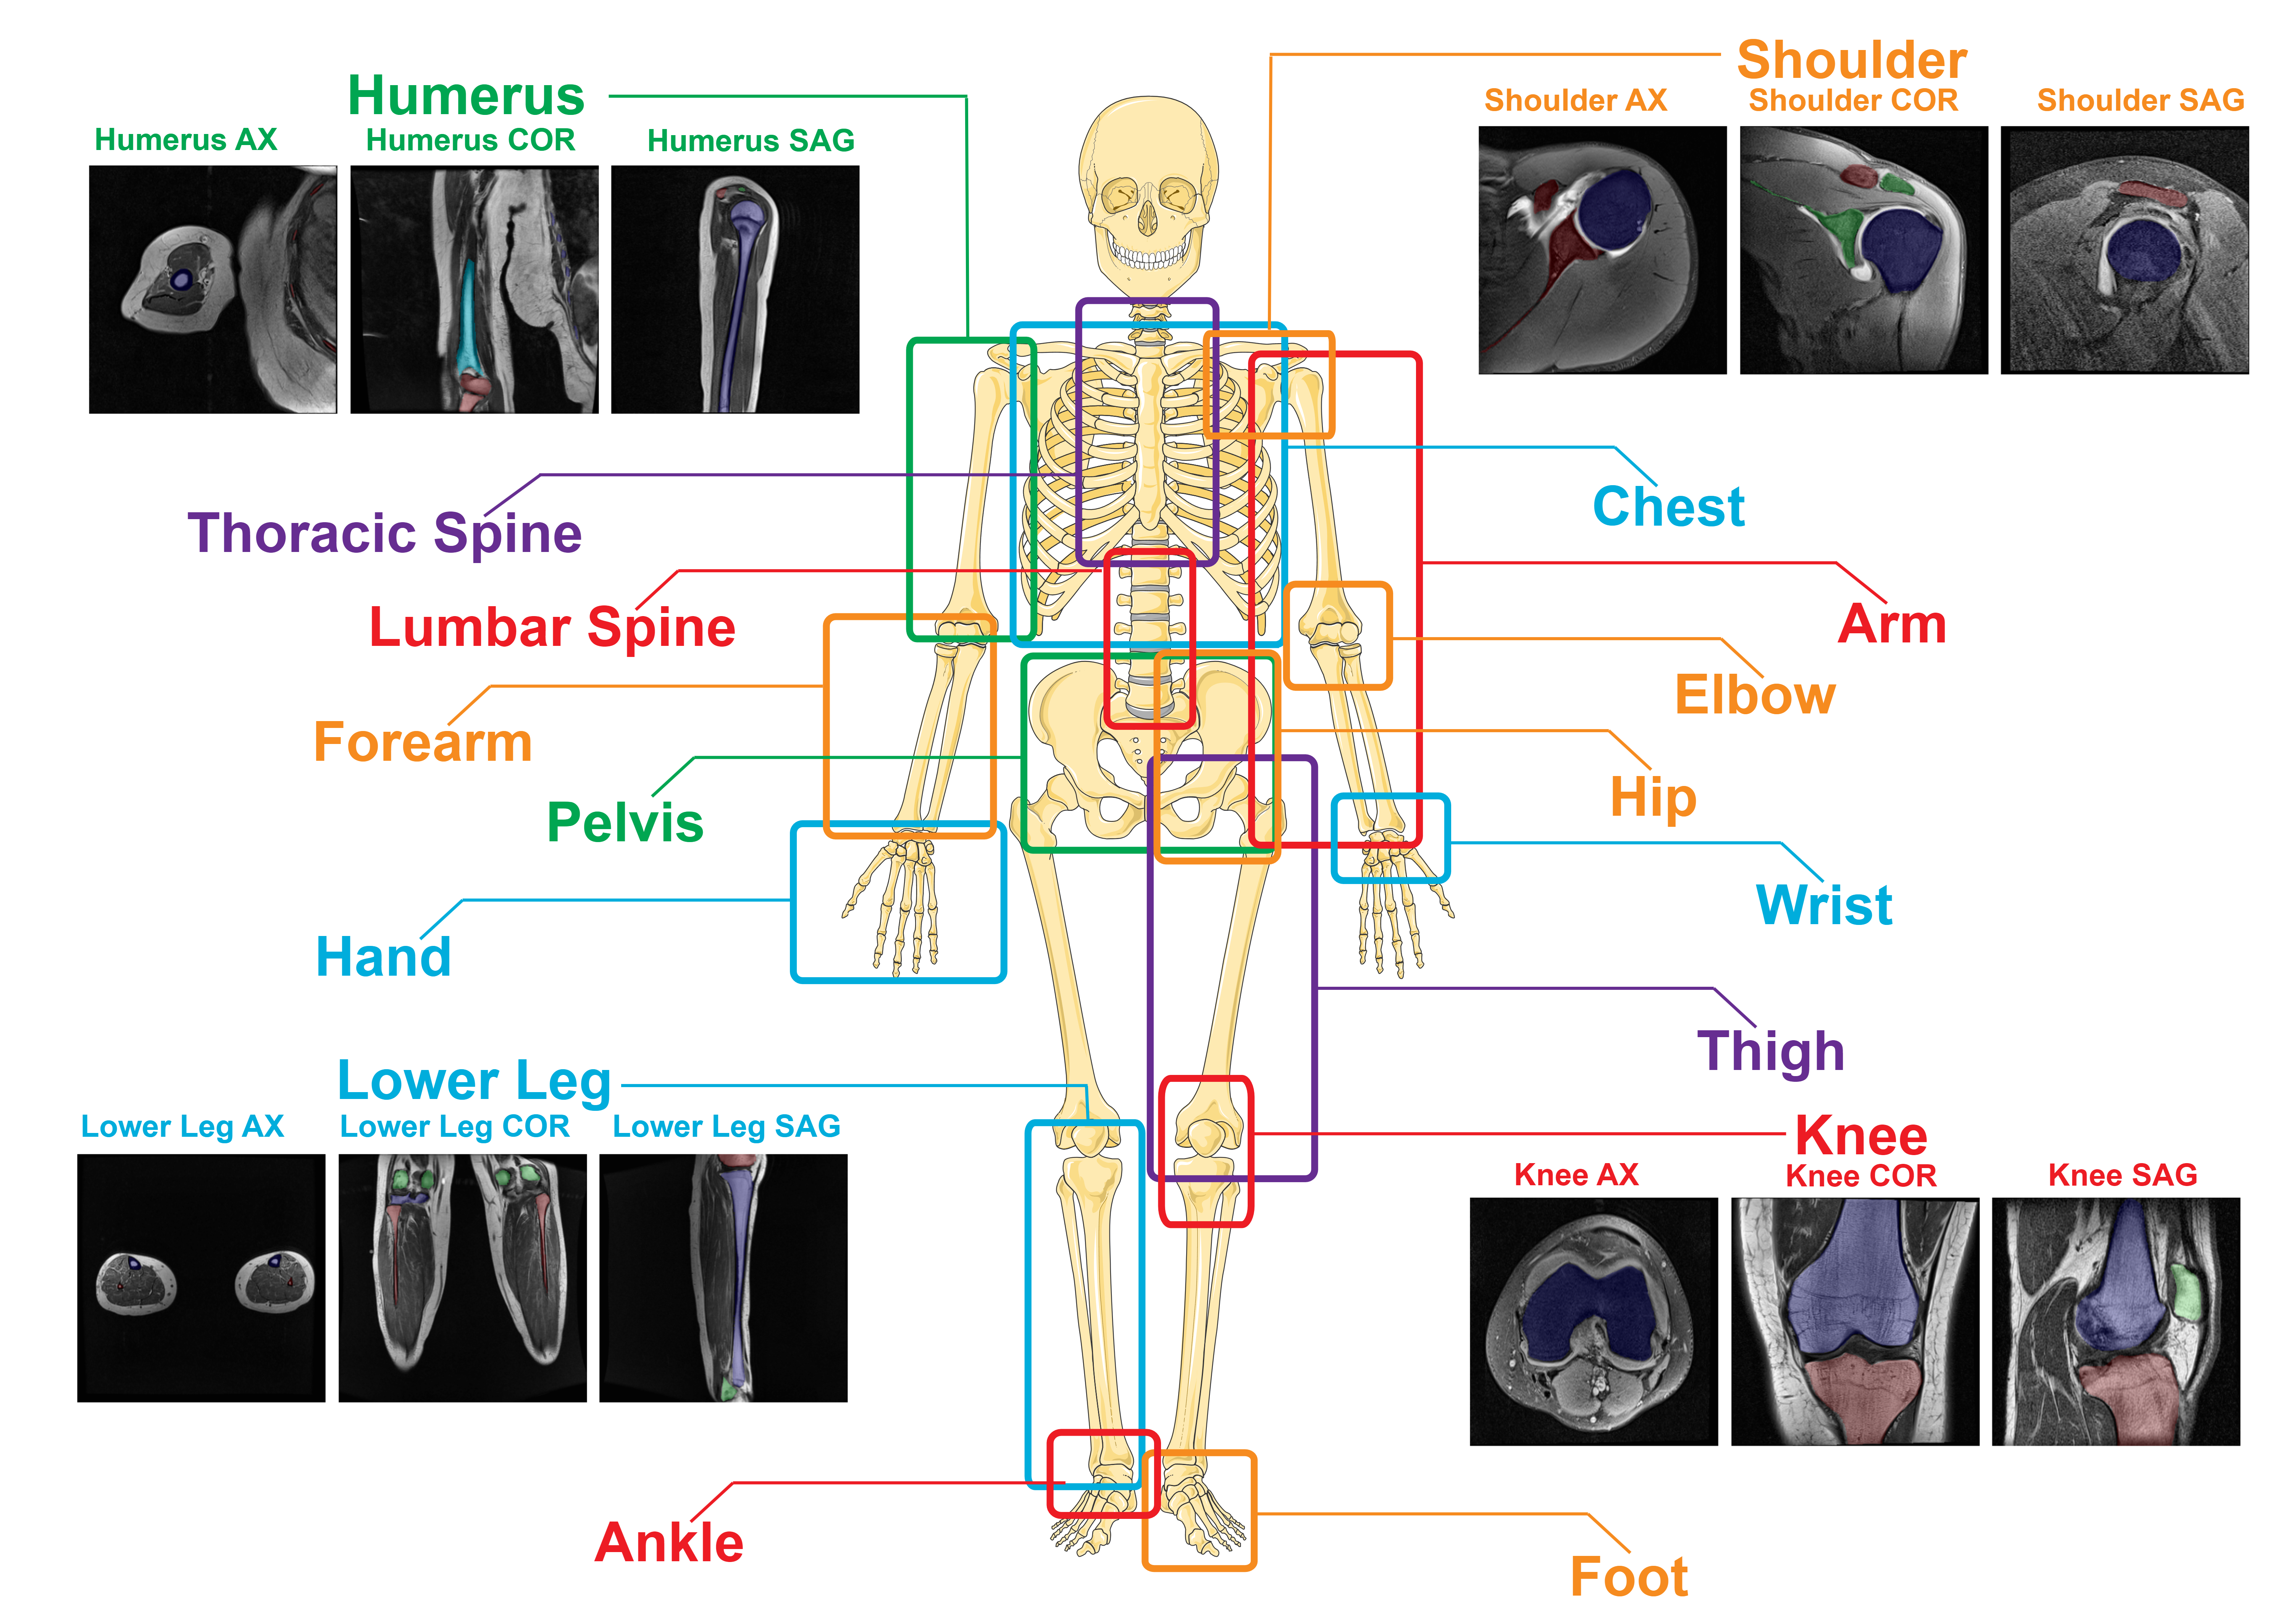

SegmentAnyBone is a foundational model-based bone segmentation algorithm adapted from Segment Anything Model (SAM) for MRI scans. It can segment bones in the following 17 body parts:

Humerus | Thoracic Spine | Lumbar Spine | Forearm | Pelvis | Hand | Lower Leg

Shoulder | Chest | Arm | Elbow | Hip | Wrist | Thigh | Knee | Foot | Ankle